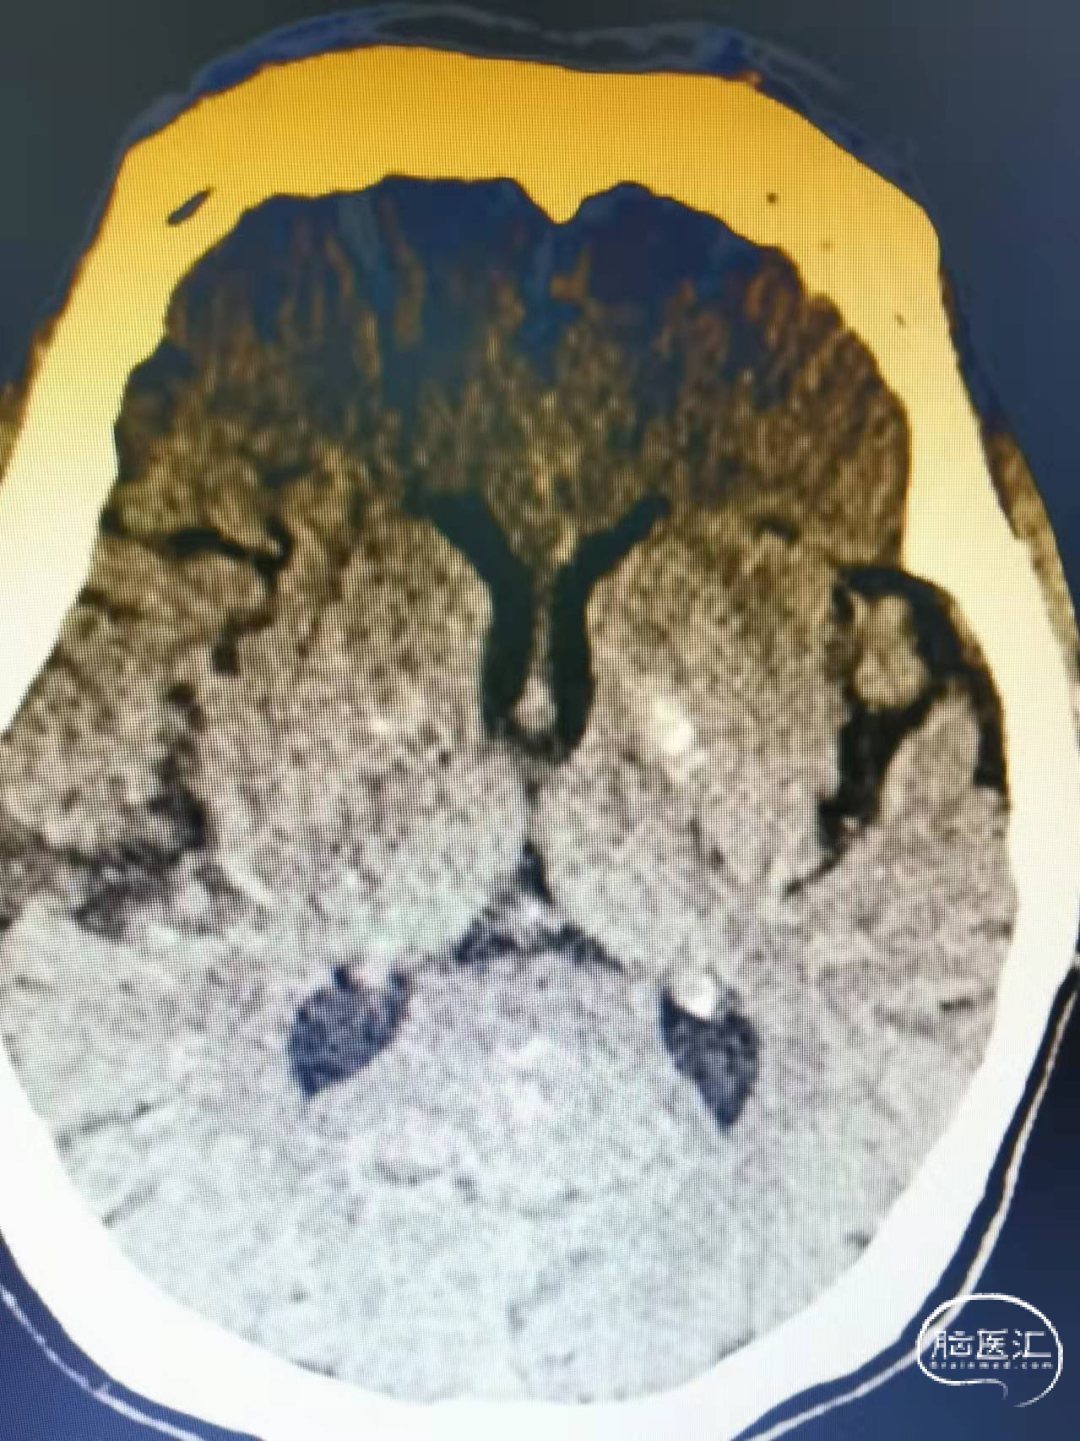

术前影像

头颅CT:左侧内囊后肢腔隙性脑梗死。

头颅MRI:双侧脑室旁异常信号。

头颅MRA:右侧大脑中动脉分叉部结节状突起。

DSA:右侧大脑中动脉分叉部动脉瘤,约3*5mm,颈宽约5mm,伴上下干起始部扩张。

大脑中动脉近端M1直径2.82mm,远端1.83mm,上干1.85mm,下干1.7mm。